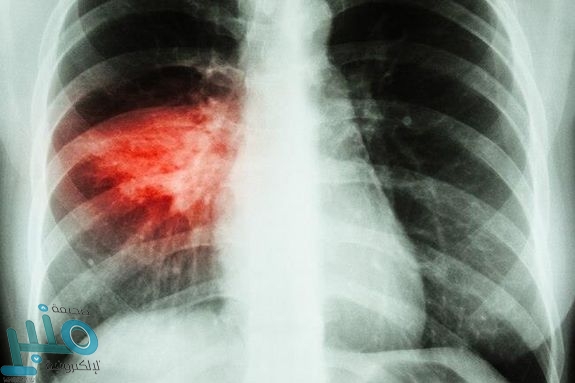

10- سرطان الرئة : يتطور سرطان الرئة بنمو خلايا الرئتين وتورمها، حيث تدمر الأنسجة السليمة من حولها. إذا أصبح الورم في الرئتين كبيرًا فقد يسد مجرى الهواء ويكون التنفس أكثر صعوبة، وقد يبدأ السرطان أيضًا في أجزاء أخرى من الجسم وينتشر إلى الرئتين، مثل سرطان الثدي.